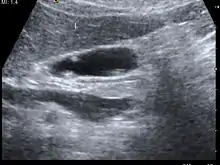

![]() ورم في المرارة كما يظهر بالموجات فوق الصوتية ورم في المرارة كما يظهر بالموجات فوق الصوتية | |

معظم تلك الأورام لا تسبب أعراضًا ملحوظة. وعادة ما يتم العثور عليها بالمصادفة عند فحص البطن عن طريق الموجات فوق الصوتية لحالات أخرى عادة ما تكون آلام في البطن.

يتم التشخيص بواسطة التصوير بالموجات فوق الصوتية، والتصوير المقطعي المحوسب.